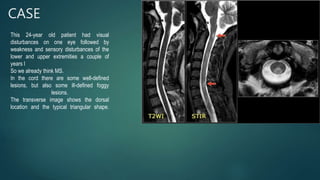

CASE

This 24-year old patient had visual

disturbances on one eye followed by

weakness and sensory disturbances of the

lower and upper extremities a couple of

years l

So we already think MS.

In the cord there are some well-defined

lesions, but also some ill-defined foggy

lesions.

The transverse image shows the dorsal

location and the typical triangular shape.